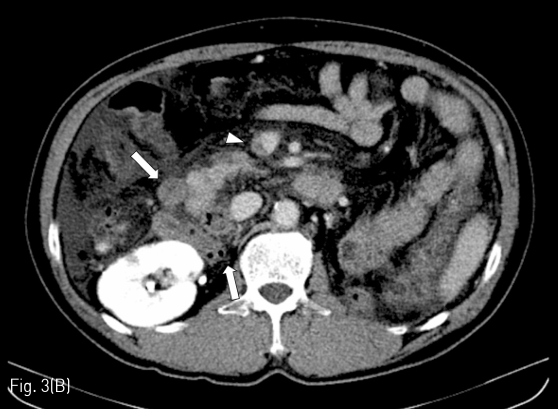

시술 전 시행한 dynamic liver CT에서 간경화 소견과 현저한 gastric varices, mesenteric-retroperitoneal varices가 관찰되었다 (Fig. 1A-C). Gastric varices는 gastro-renal shunt가, mesenteric-retroperitoneal varices는 meso-caval shunt가 각각의 경로로 생각되었다. Meso-caval shunt는 superior mesenteric vein (SMV)에서 right renal vein을 거쳐 inferior vena cava (IVC)로 유출되는 것으로 판단하였다. Esophageal varices도 보이긴 하였으나 경미한 정도였다.

Fig 1B

(A-C) Contrast-enhanced CT images obtained before PARTO show gastric varices (black arrows) and mesenteric-retroperitoneal varices (white arrows). Arrow head indicates dilated SMV. Curved arrow indicates the meso-caval shunt.